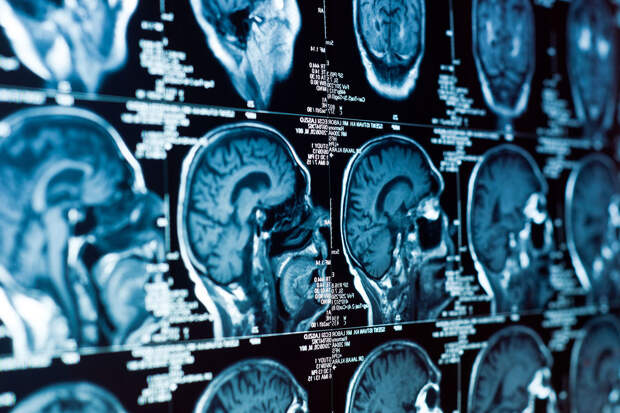

Испытуемых обследовали дважды: после бессонной ночи и полноценного отдыха. В ходе эксперимента участники выполняли задания на внимание, одновременно проходя функциональную МРТ (магнитно-резонансную томографию) и ЭЭГ (исследование электрической активности мозга). Также фиксировались пульс, дыхание и реакция зрачков.Как и ожидалось, участники, не спавшие всю ночь, допускали больше ошибок и медленнее реагировали на сигналы. Исследователи обнаружили, что в моменты потери концентрации после бессонной ночи происходил отток ликвора (цереброспинальной жидкости) от мозга. В норме этот процесс запускается во время сна и помогает очищать мозг от продуктов обмена.